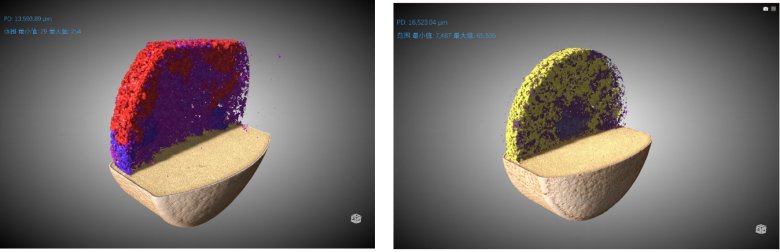

② 推動(dòng)劑結(jié)構(gòu)形態(tài)

左圖為原研藥,右圖為仿制藥。顏色為隨機(jī)染色

從上面的圖片、動(dòng)畫以及數(shù)據(jù)我們可以得到如下一些信息:

1、 原研藥的整體孔隙率是大于仿制藥的 (2.79% Vs 1.70%)

2、兩款藥的孔隙分布都是隨著孔徑增大而減少的趨勢,但仿制藥的孔徑分布中位數(shù)要明顯小于原研藥

3、原研藥的推動(dòng)劑整體占比也是大于仿制藥的 (5.11% Vs 3.60%)

4、仿制藥的推動(dòng)劑顆粒均勻度好過于原研藥